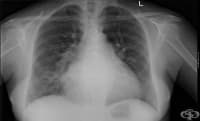

Саркоидозата (болест на Besnier-Boeck-Schaumann) е хронично мултисистемно грануломатозно заболяване,...

Въведение и исторически преглед Саркоидозата (sarco плът, месо; eidos подобно; osis състояние) е мул...